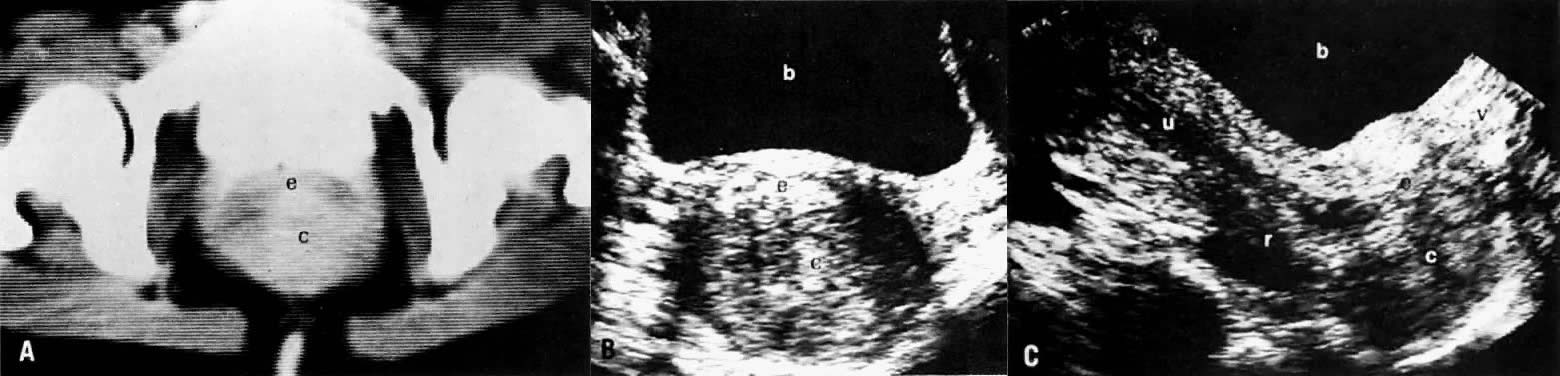

Cervical enlargement (see Fig. 2B; Fig. 5A) is a typical finding of cervical carcinoma on computed tomography (CT). After intravenous contrast material administration, necrotic soft-tissue masses of the cervix can be identified as low attenuation areas.8 Despite technical advances in CT, its accuracy for detecting cervical tumors, which has been reported to be 63% to 80%, remains less than that of the clinical, ultrasound, or MRI examination.9,10

Fig. 5. Cervical carcinoma stage IB. CT scan of the pelvis ( A) shows a well-marginated posterior cervical mass stretching the cervical canal anteriorly. Transverse ( B) and sagittal ( C) sonograms of the pelvis show a large, well-defined, inhomogeneous, solid posterior cervical mass stretching the cervical canal anteriorly. It appears confined to the cervix without parametrial spread. The relationship of the mass to the vagina, uterus, rectum, and bladder is best demonstrated on the sagittal view. ( c, cervical mass; e, cervical canal; v, vagina; u, uterus; r, rectum; b, bladder.)

In locally confined disease, a cervical mass may be seen by ultrasound (Fig. 5B and C). In locally advanced disease, the cervix may become diffusely enlarged, inhomogeneous, and irregularly marginated (Fig. 6A and B).

Poor soft-tissue contrast and restriction to the axial plane limit the ability of CT to determine the depth of stromal invasion or to assess tumor volume. Tumor confined to the cervix may be seen as an inhomogeneous, hypodense area in an enlarged cervix; however, the size of the cervix cannot be used in staging cervical carcinoma. The criteria used to stage confined disease include smooth, well-defined cervical margins; no prominent parametrial soft-tissue strands; no parametrial soft-tissue mass; and preservation of the periureteral fat planes (see Fig. 5A).22 CT has a limited role, however, in the detection of tumor extension into the vagina and body of the uterus.

LOCAL ULTRASOUND STAGING.

Ultrasound may play a role in the evaluation of tumor extension to the parametrium and the pelvic sidewall in patients with an equivocal pelvic examination.38,39 In stage IB, the tumor is confined to the cervix on ultrasound, without parametrial extension (see Fig. 5B and C). In stage IIB, a tongue of the hypoechoic soft-tissue mass extends laterally from the cervix (see Fig. 6B). More recently, high-resolution transrectal ultrasound was found to be more sensitive in assessing parametrial tumor spread compared to clinical evaluation (78% vs 52%, respectively).40 Ultrasound is also capable of detecting tumor extension into the bladder (Fig. 20),39,41 hydronephrosis (Fig. 6C),38 and/or ureteral obstruction (see Fig. 6B). Unlike CT, however, it cannot always reliably evaluate the level and cause of the obstruction.